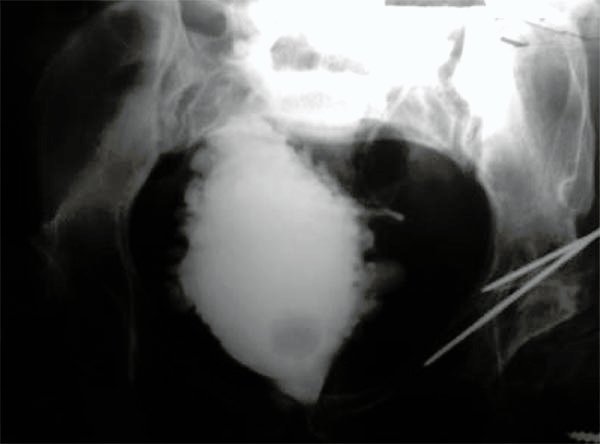

Figura 3:

Cistografía paciente n°5.